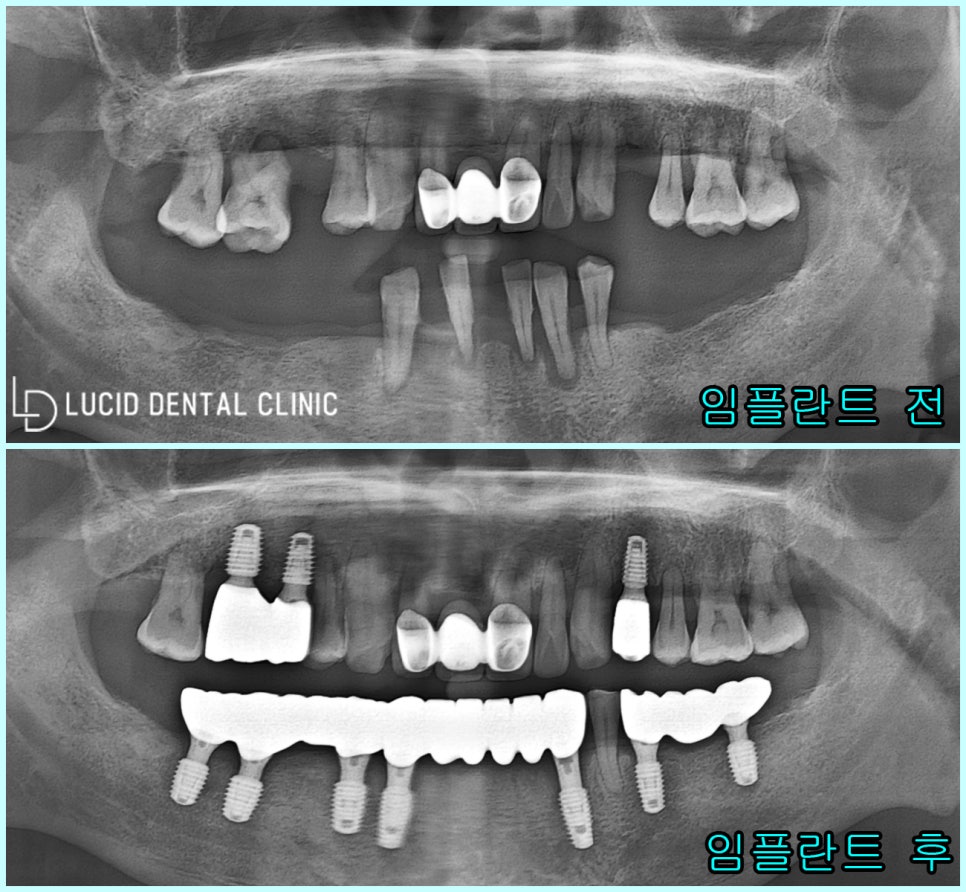

- 검진 결과 및 진단

<파노라마 엑스레이의 경우,

본래 환자의 구강과 반대로 나오니

사진을 기준으로 설명하겠습니다.>

진단 결과, 현재 환자 구강 속에

치근단 염증(뿌리 주변)

심한 치조골 퇴행(내려감)

이미 발치하여 빈 어금니

총 3가지의 문제를 발견할 수 있었습니다.

잔존치 역시 정출이 시작되며 보존이 어려웠고

잔존 치조골의 양 또한 현저히 적어 보였습니다.

진단 결과를 토대로 함께 계획을 수립한 결과,

위, 아래 어금니 임플란트 수술 을 계획했습니다.

- 최종 종료

환자의 나이 및 회복 능력을 고려하여

조금씩 나눠서 치료를 진행했었는데요

그 결과, 한층 더 나은 방향으로

결과가 나올 수 있었던 것 같아

저도, 환자도 크게 만족스러웠던

치료 중 하나였다고 생각합니다 :)

실제로 초진 구내 모습과 비교하면

심미는 물론, 기능까지 온전하게

되찾은 모습을 볼 수 있습니다.